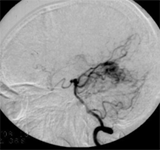

先天性腦血管畸形--造影

先天性腦血管畸形--造影二、用藥原則

1.青少年患者,有頭痛、癲癇和蛛網腔下腔出血史。2.臨床表現有急性顱內自發出血、或癲癇發作、或明顯局源體徵者。3.頭部CT:平掃病變常為低密度、周圍亦有低密度,若腦內出血可見高密度,增強後血管區呈高密度,有時可見供血動脈和引流靜脈。4.頭部MRI:優於CT,不僅能顯示畸形血管及其周圍腦組織,還可區別出血與鈣化。MRI血管造影相可提高畸形血管團的診斷率。5.腦血管造影:最可靠、最重要的診斷方法,動脈期可見血管團、供血動脈及早期顯現的引流靜脈。

1.頭顱平片顯示顱內板受侵蝕及腦膜中動脈迂曲變寬,提示畸形血管可能。2.頭部CT可發現血腫及提供畸形血管的可能性。3.頭部磁共振:優於CT,不僅能顯示畸形血管及其與周圍腦組織的關係,還可區別出血與鈣化。4.腦血管造影是本病最可靠和主要的診斷方法,並能行血管內介入治療。